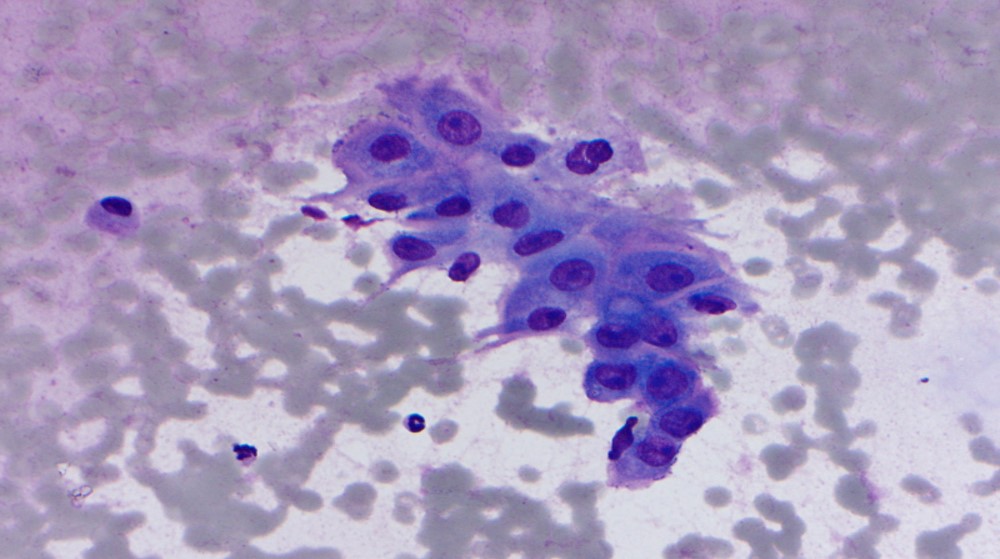

The specimen is cellular and consists of clusters and sheets of large atypical cells with macronucleoli and moderate amounts of somewhat dense cytoplasm. Occasional cells appear to have intracellular mucin and represent muciphages. Scattered benign ductal cells and acini are noted. Necrosis is absent. These findings are consistent with a high-grade salivary gland neoplasm, and a high-grade mucoepidermoid carcinoma is favored on cytology. Subsequent resection confirmed the cytomorphologic impression and showed also perineural invasion.

Mucoepidermoid carcinoma is the most common salivary gland malignancy in children and adults, and the most common malignancy of major and minor salivary glands. Low-grade tumors are more commonly cystic, while high-grade tumors are solid and infiltrative. The diagnostic feature is the combination of mucous cells, epidermoid/squamoid cells, and intermediate cells (which resemble squamous metaplastic cells). High-grade mucoepidermoid carcinomas have a greater proportion of squamoid cells with more cytologic atypia.